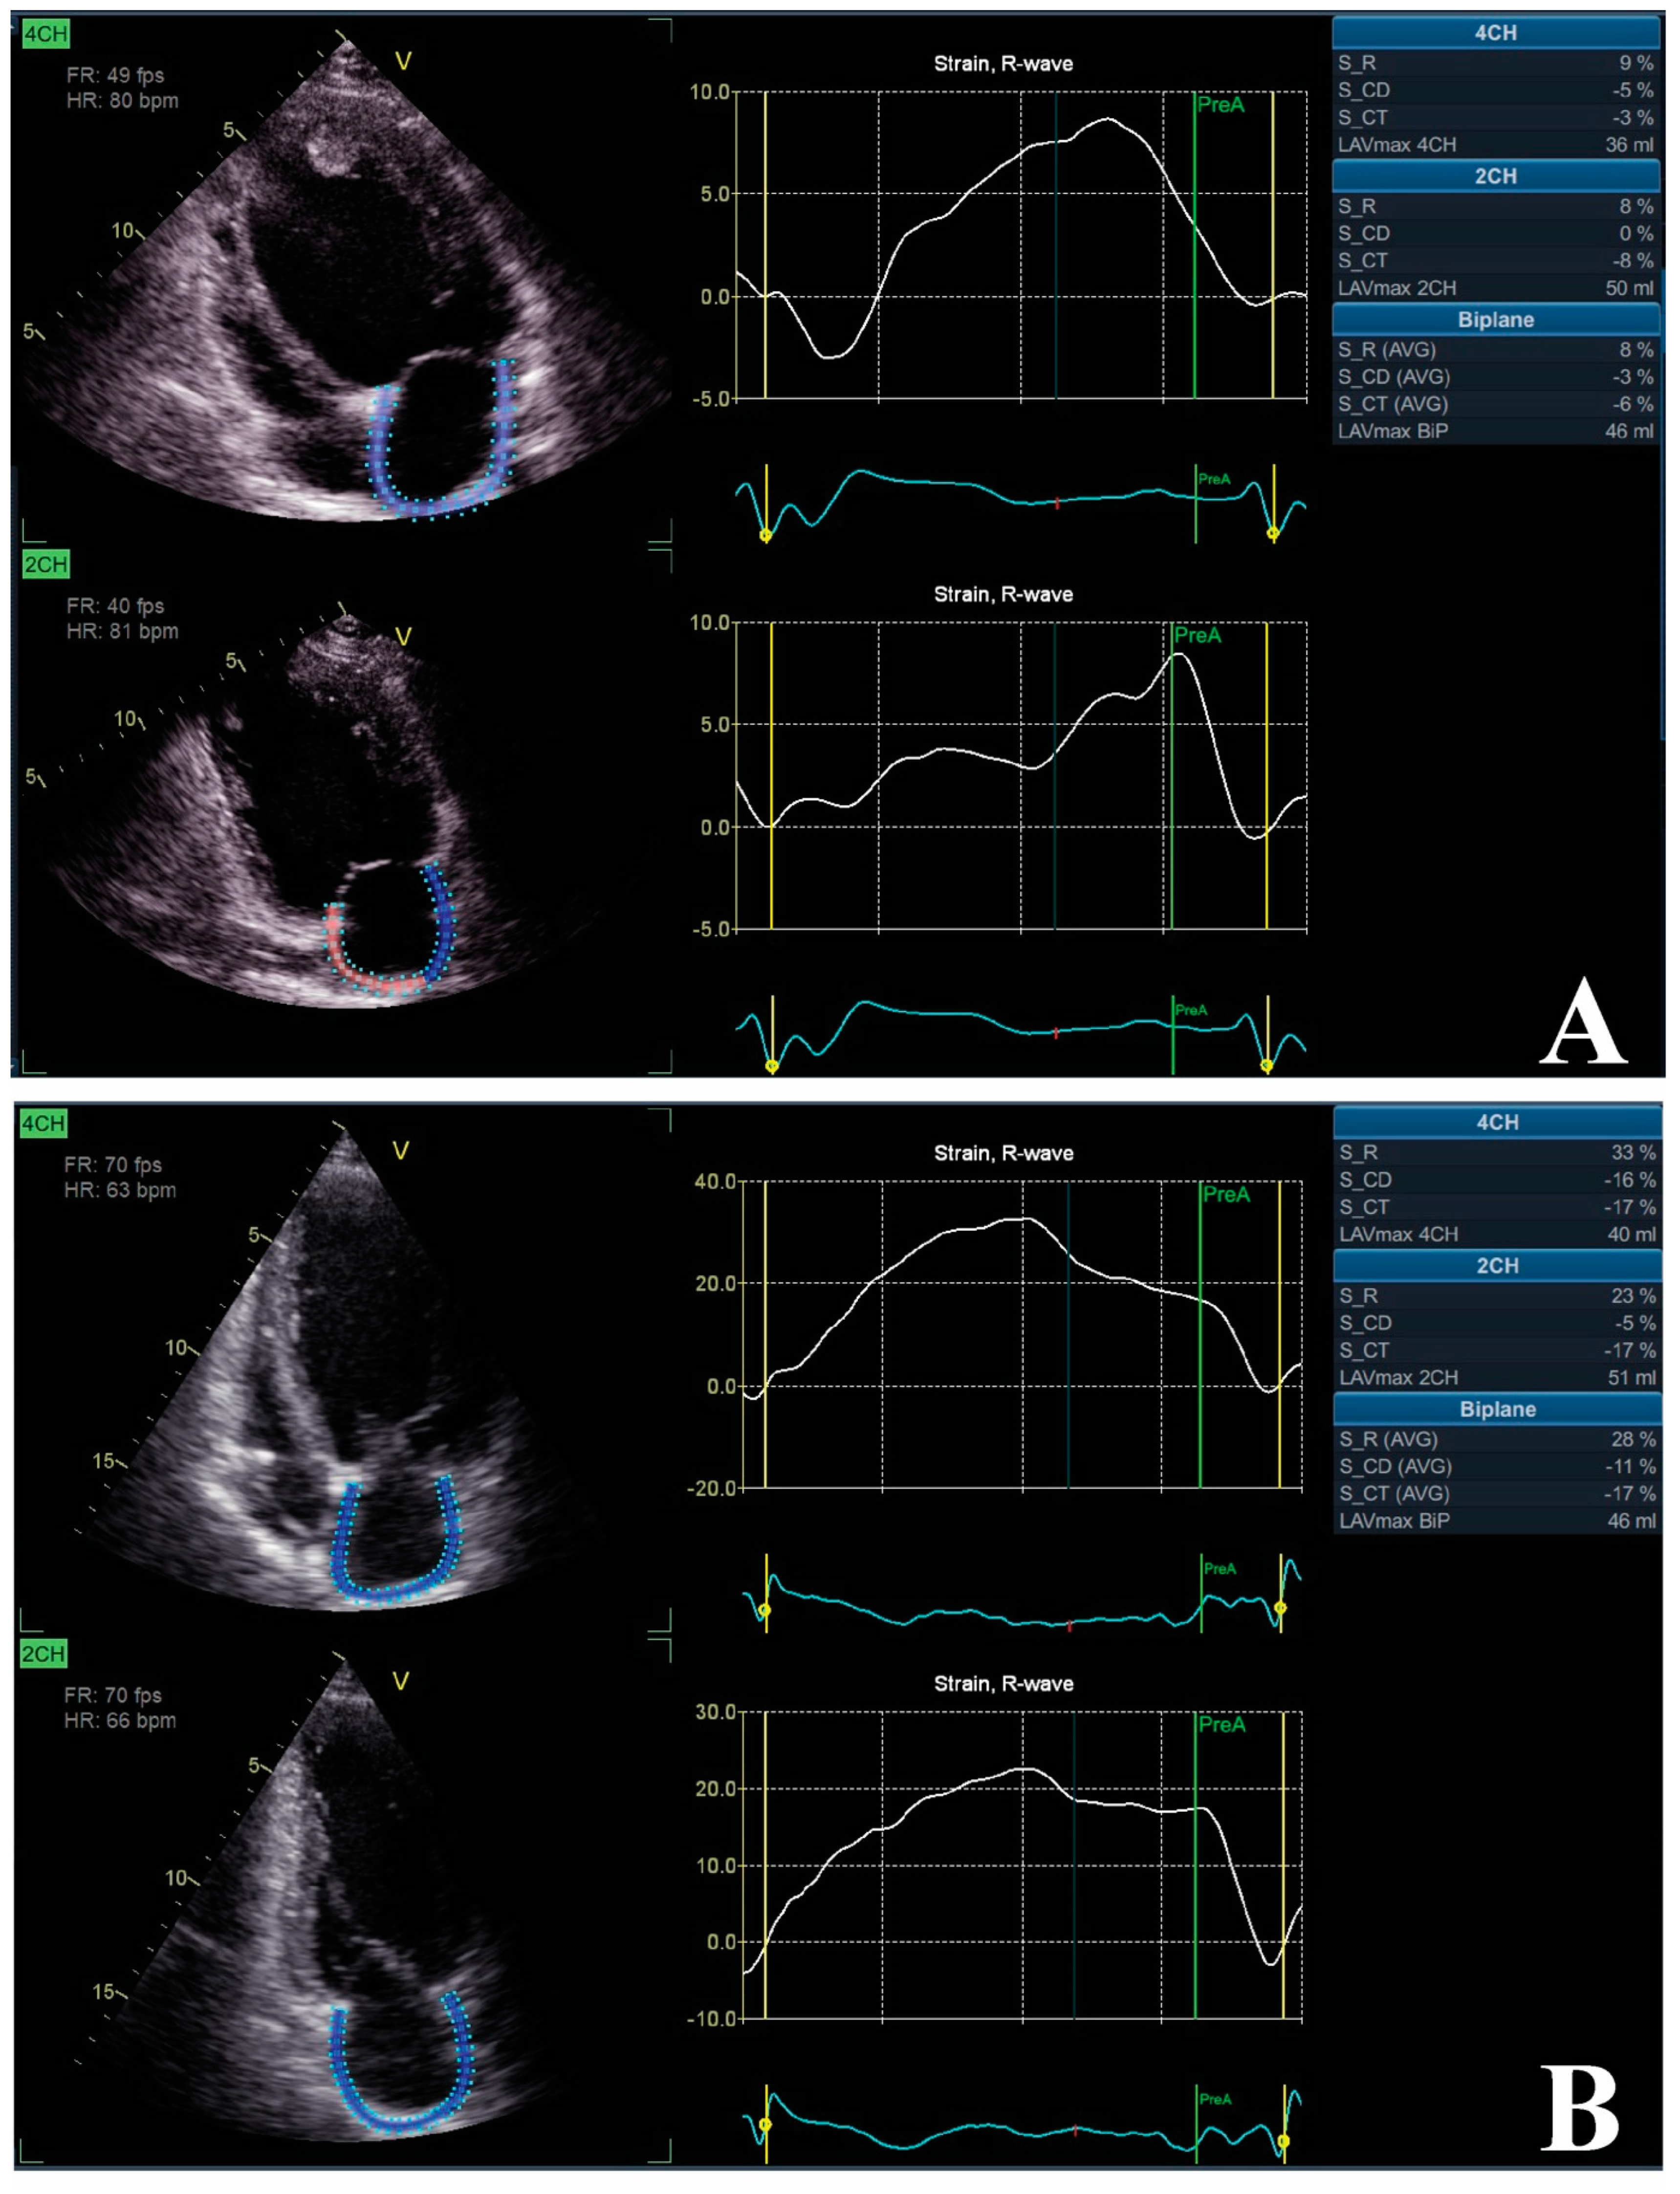

- Feneon, D.; Behaghel, A.; Bernard, A.; Fournet, M.; Mabo, P.; Daubert, J.-C.; Leclercq, C.; Donal, E. Left atrial function, a new predictor of response to cardiac resynchronization therapy? Heart Rhythm 2015, 12, 1800–1806. [Google Scholar] [CrossRef]

- Valzania, C.; Gadler, F.; Boriani, G.; Rapezzi, C.; Eriksson, M.J. Effect of Cardiac Resynchronization Therapy on Left Atrial Size and Function as Expressed by Speckle Tracking 2-Dimensional Strain. Am. J. Cardiol. 2016, 118, 237–243. [Google Scholar] [CrossRef]

| Feneon et al. | [86] | 2015 | 79 | LAS-r LA pre-ejection index | 6 Mo to evaluate the impact of CRT on LA strain | LAS-r was a good predictor for CRT responsiveness, regardless of cardiac pathology |

| Valzania et al. | [87] | 2016 | 30 | LAS-r | 12 Mo for the impact of CRT on LA strain and the relationship with some parameters | CRT responsiveness had beneficial impact on LA size and LAS-r. LV function, filling pressures, and mitral regurgitation significantly influenced LA remodeling |

| Dokuni et al. | [85] | 2020 | 90 | LAS-r LAPF | 6 Mo for the role of CRT on LA strain function | CRT reduced LA dyssynchrony, which in turn improved LAS-r and LAPF |